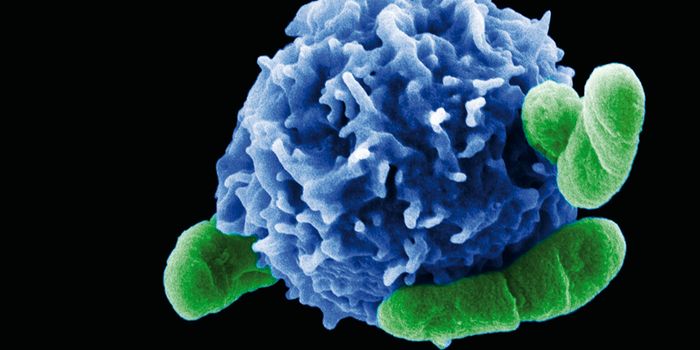

APR 30, 2017ImmunologyIntroducing a new role for macrophages, immune cells in charge of engulfing pathogens and “biological waste” ...

JAN 19, 2022Cell & Molecular BiologyImmune cells called macrophages are on the front lines of our body's defense system; macrophages can detect pathogens an ...